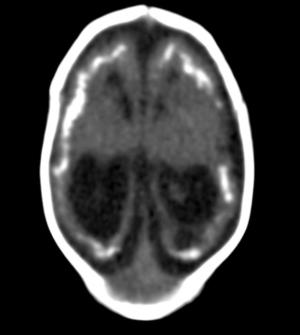

The first study looks at CT findings of the central nervous system in 16 newborn babies with congenital Zika virus infection confirmed by tests in cerebral spinal fluid.

The researchers identified a pattern of CT brain findings in the babies, including decreased brain volume, simplified gyral pattern, calcifications, ventricular dilatation and prominent occipital bone.

"We live in Pernambuco, a state in northeastern Brazil, which had the highest number of patients with microcephaly during the Zika outbreak in our country," said study author Natacha Calheiros de Lima Petribu, M.D., from the Department of Radiology at Barão de Lucena Hospital. "Our study proves that Zika virus infection can cause congenital brain damage in babies with and without microcephaly."